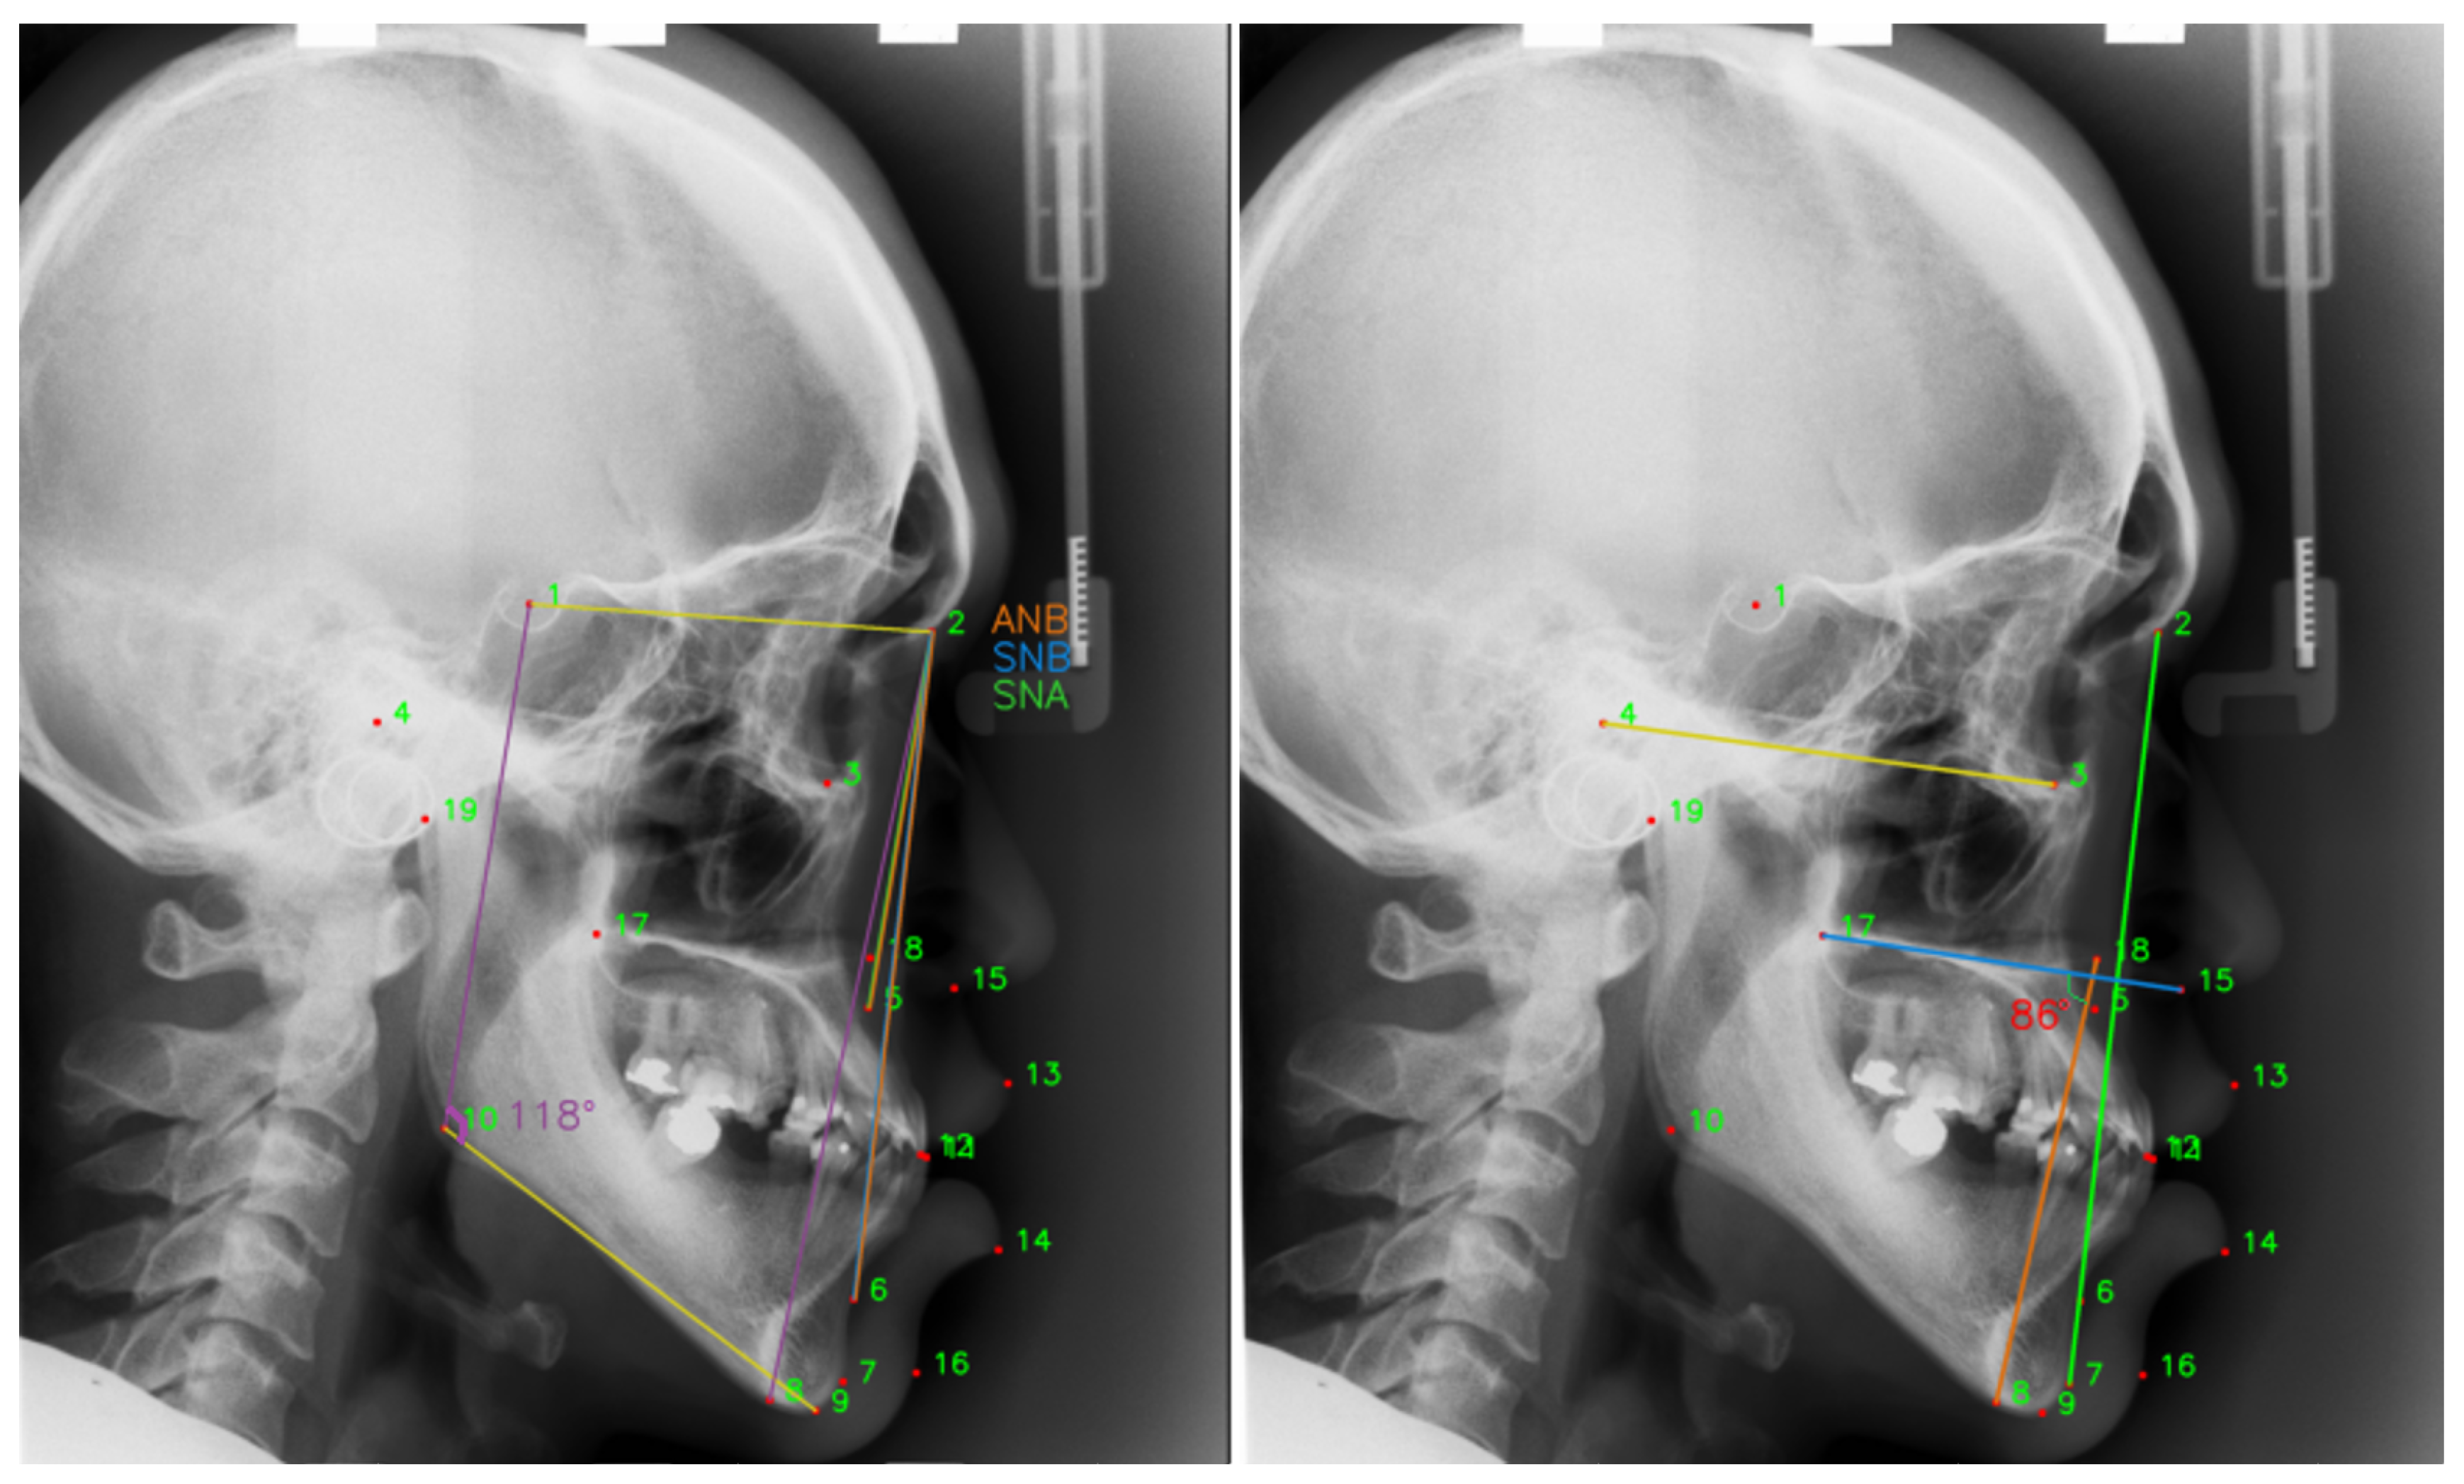

| Anatomical Name | Sella | Nasion | Orbitale | Porion | Subspinale | Supramentale | Pogonion | Menton | Gnathion | Gonion |

| Number | L11 | L12 | L13 | L14 | L15 | L16 | L17 | L18 | L19 | |

| Anatomical Name | Lower incisal incision | Upper incisal incision | Upper lip | Lower lip | Subnasale | Soft tissue pogonion | Posterior nasal spine | Anterior nasal spine | Articulate |